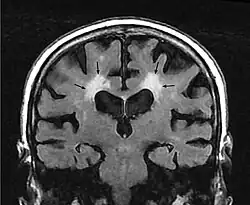

Leukoaraiosis is a particular abnormal change in appearance of white matter near the lateral ventricles. It is often seen in aged individuals, but sometimes in young adults.[1][2] On MRI, leukoaraiosis changes appear as white matter hyperintensities (WMHs) in T2 FLAIR images.[3][4] On CT scans, leukoaraiosis appears as hypodense periventricular white-matter lesions.[5]

The term "leukoaraiosis" was coined in 1986[6][7] by Hachinski, Potter, and Merskey as a descriptive term for rarefaction ("araiosis") of the white matter, showing up as decreased density on CT and increased signal intensity on T2/FLAIR sequences (white matter hyperintensities) performed as part of MRI brain scans.

These white matter changes are also commonly referred to as periventricular white matter disease, or white matter hyperintensities (WMH), due to their bright white appearance on T2 MRI scans. Many patients can have leukoaraiosis without any associated clinical abnormality. However, underlying vascular mechanisms are suspected to be the cause of the imaging findings. Hypertension, smoking, diabetes,[3] hyperhomocysteinemia, and heart diseases are all risk factors for leukoaraiosis.